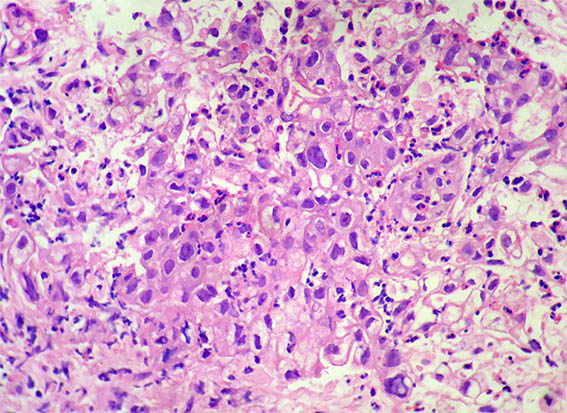

Figura 1. H&E, X100.

Figura 2. H&E, X100.

Figura 3.

H&E, X100.

Figura 4. H&E, X200.

Figura 5. H&E, X200.

Figura 6. H&E, X200.

Figura 7. H&E, X400.

Figura 8. H&E, X400.

Figura 9. H&E, X400.

Figura 10. H&E, X400.